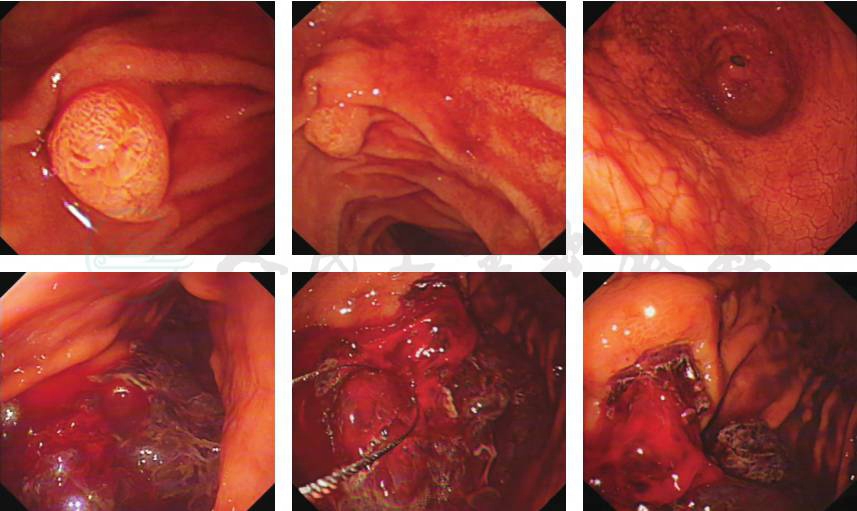

胃镜检查:见胃腔内大量暗红色血凝块。反复清洗及清理胃腔,于胃体中段前壁近大弯侧见一巨大隆起性病灶,表面溃疡形成,有活动性出血。予活检,并加1支去甲肾上腺素于盐水给予局部喷洒后,不见活动性出血后退镜。其余未见明显异常(图5)。送检活检组织镜下见侵袭性B细胞淋巴瘤(图6):肿瘤细胞中等大,核圆形,卵圆形可见小核仁,核分裂象多见,可见星空现象,结合免疫组化及荧光原位杂交(fluorescence in situ hybridization,FISH)检测结果,符合伯基特淋巴瘤(Burkitt lymphoma,BL),待结合临床诊断。免疫组化结果:肿瘤细胞分化簇(cluster of differentiation,CD)20、CD19、CD10、Bcl6阳性,Bc12部分弱阳性,C-myc约 85%阳性,Ki-67近100%阳性,CD3、CD5、MUM1、CyclinD1、CD30、ALJ、肌酸激酶(creatine kinase isomer,CK)、CD21阴性。原位杂交结果:EBER阴性。FISH检测结果:存在C-MYC基因断裂分离,不存在BCL-6、BCL-2基因断裂分离。

图5 胃镜检查